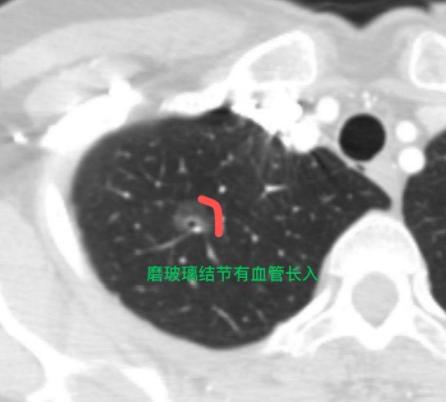

这样的肺磨玻璃结节,考虑是早期肺癌,怎么还会被误诊?这位57岁的女士专程从外地来找我。 其实她前年体检就发现了一个8mm的磨玻璃结节,当时当地医生告诉她“是炎症”,她也就放心了,没再去管。 前段时间,她偶然刷到我的科普,自己对着CT片子越看越不对劲,越想越焦虑,饭也吃不下、觉也睡不好,赶紧让家人挂了我的号,坐飞机赶了过来。 像她这样的情况,我在门诊真的遇到不少!也特别感谢大家的信任,这让我更加坚定“坚持做科普,真的能帮助到大家”。 仔细对比她前年和现在的CT片子,我发现这个结节有空泡,还有血管穿行,是个比较典型的早期肺癌表现,而且比之前饱满了一些,说明可能在进展,甚至已经有浸润成分了。 一听到“肺癌”两个字,她当场就哭了,紧张地问我:“是不是活不了多久了?” 我赶紧安慰她:“别担心,这种结节通常发展非常慢,现在切掉基本上就能痊愈,术后也不需要额外治疗,不影响正常生活的。” 听我这么一说,她情绪才慢慢平复,接着就催着我尽快安排手术,一下子又有了精神,状态完全不一样了。 后续我们为她做了“单孔胸腔镜下右上肺段切除”,手术很顺利。 通过这个病例,我也想提醒大家:只要查出磨玻璃结节,无论当时考虑是炎症还是惰性结节,都一定要定期随访,千万别直接不管。一旦复查发现它长大了、变实了,就要考虑手术干预。 我经常说一句话:“战略上藐视,战术上重视。”放在肺结节管理上也一样,不必过度恐慌,但也不能完全放任。[玫瑰][谢谢]胸外科乔贵宾医生肺结节[超话]